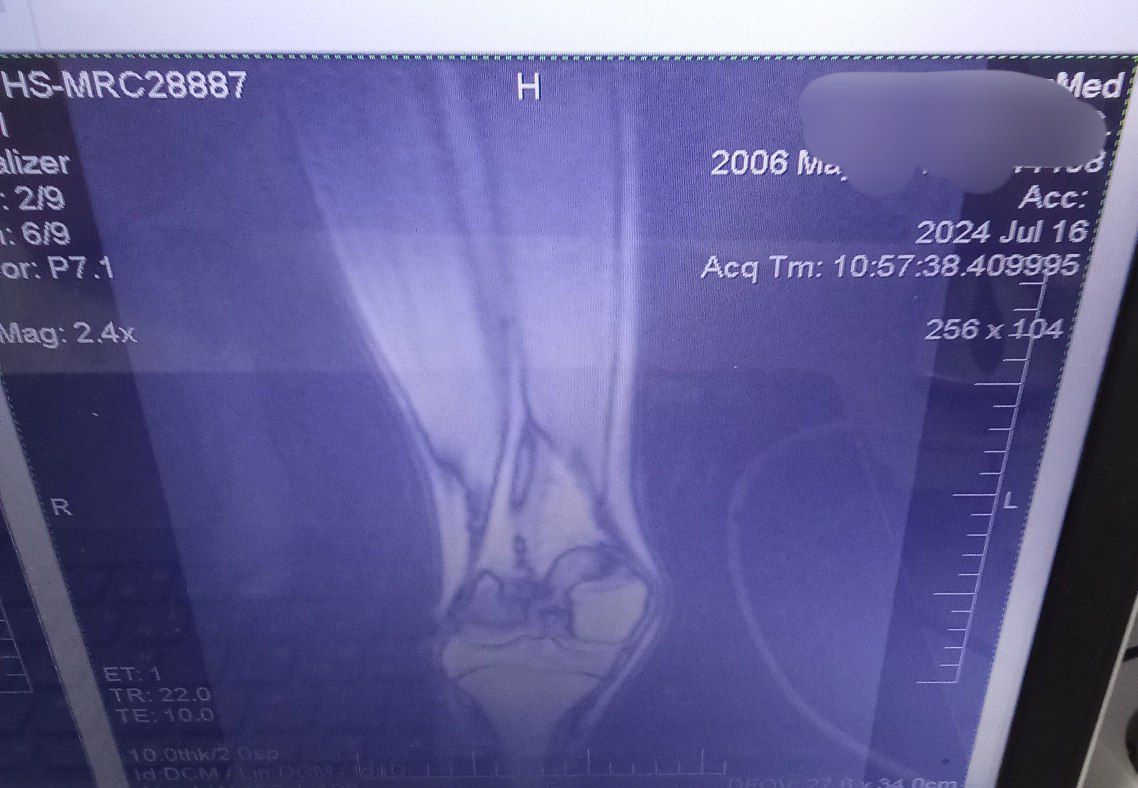

У меня такая же хуйня, но куда хуже, с рождения двухсторонняя дисплазия, в лет 11 началось проявление вальгусной деформации ног, спустя год стали вылетать надколенники (чашечки). С каждым годом это все ухудшалось и ухудшалось. Родители особо не торопились меня отводить к врачам, по этому к 14 я утратил способность нормально ходить (вечный страх что вот вот вылетит колено и я упаду) бегать я вовсе не могу, потому что надколенники сместились латерально кверху, по этому стабильность моих ног начинает качать уже от обычного ветра. Из за этого я не смог подписать контракт в 18 как и хотел, но начал процесс какого либо контакта с врачами и поиска решения проблемы без мам и пап. Сам выбивал справки и направления на бесплатные обследования. Спустя 4 месяцев сбора кучи обследования, пару рентгенов, пару мрт и одного торсиального кт. Мой хирург который взял меня под свое крыло, увидел во мне необычайно удивительный случай. Моментально уехал в Москву, там на какой то крутой конференции, он показал мои результаты обследований и видео подвижности моих ног другим врачам и как он передал, там все ахуели. Предложил мне относительно сложную операцию, типичная остеотомия, только пилить будут в двух местах бедро, в трёх большеберцовую кость и резекцию икры для предотвращения спазма нервов ну и замена связок на надколеннике. В итоге, мне остаётся букалаьно две недели до госпитализация и две недели и один день до операции. Я очень волнуюсь, потому что я забыл что уже такое бегать, что такое прыгать и ходить без страха вывихнуть колено.

IMG202507271253[...].jpg 97Кб, 577x1280

IMG202507271253[...].jpg 228Кб, 1280x960

IMG202507271253[...].jpg 195Кб, 960x1280

IMG202507271253[...].jpg 182Кб, 960x1280

IMG202507271253[...].jpg 183Кб, 1217x959

IMG202507271253[...].jpg 199Кб, 1224x892

IMG202410312014[...].jpg 25Кб, 299x781

IMG202507271253[...].jpg 126Кб, 1138x788